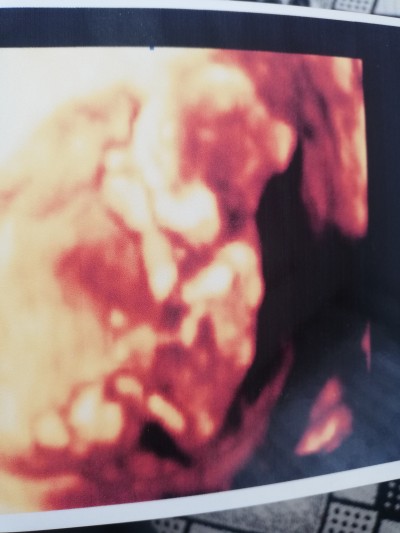

13 haftalığız nub teorisi ile bakacak olan var mı cinsiyete bakacak 2 fotoğraf var

image

Benim teorim e göre kız :) sağlıkla gelsin minnak <3

Kız bebek.